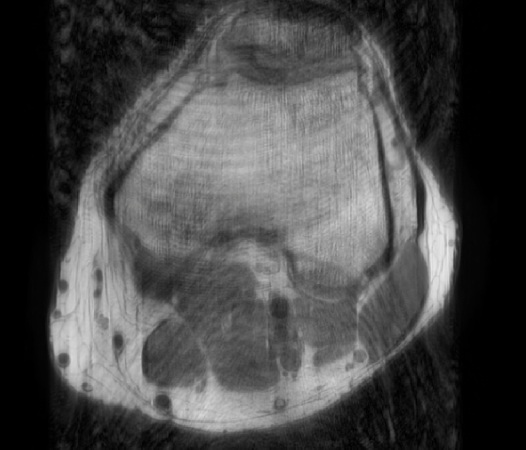

In the example below, only one fifth of the required MR radiofrequency signals is recorded. This results in a five times faster acquisition, with a subsampled k-space (top left) and inherent image artifacts after standard reconstruction (top right).

Knee compressed sense

The Compressed SENSE reconstruction then uses iterative, knowledge-based algorithms to fill in the empty lines in k-space (bottom left). This removes the artifacts while keeping the final image fully consistent with the acquired data (bottom right).